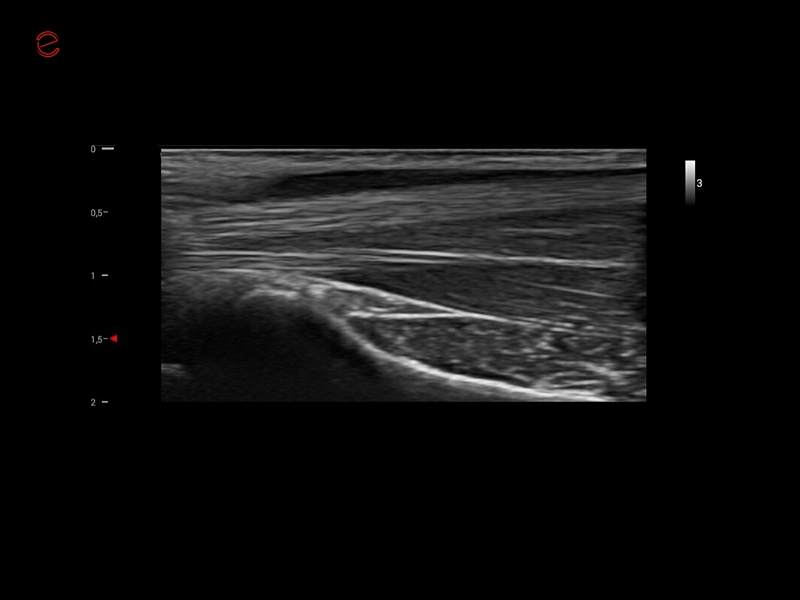

MyLab™X1 Go - Cardiovascular IMT

MyLab™X1 Go - Cardiovascular IMT